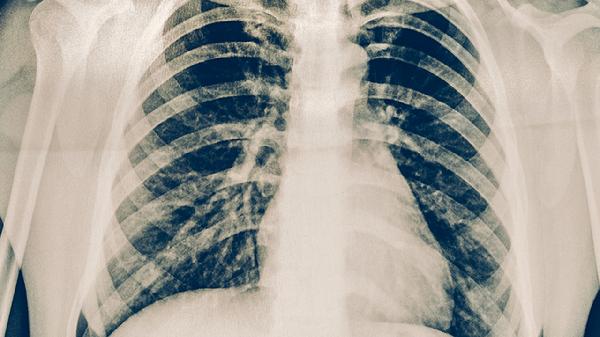

极少数免疫功能健全的个体接触少量结核菌后,可能通过自身免疫清除病原体,但这种情况无法预测且缺乏临床证据支持。多数无症状感染者需通过结核菌素试验、γ-干扰素释放试验或影像学检查发现病灶,确诊后应完成6-9个月的抗结核药物治疗。